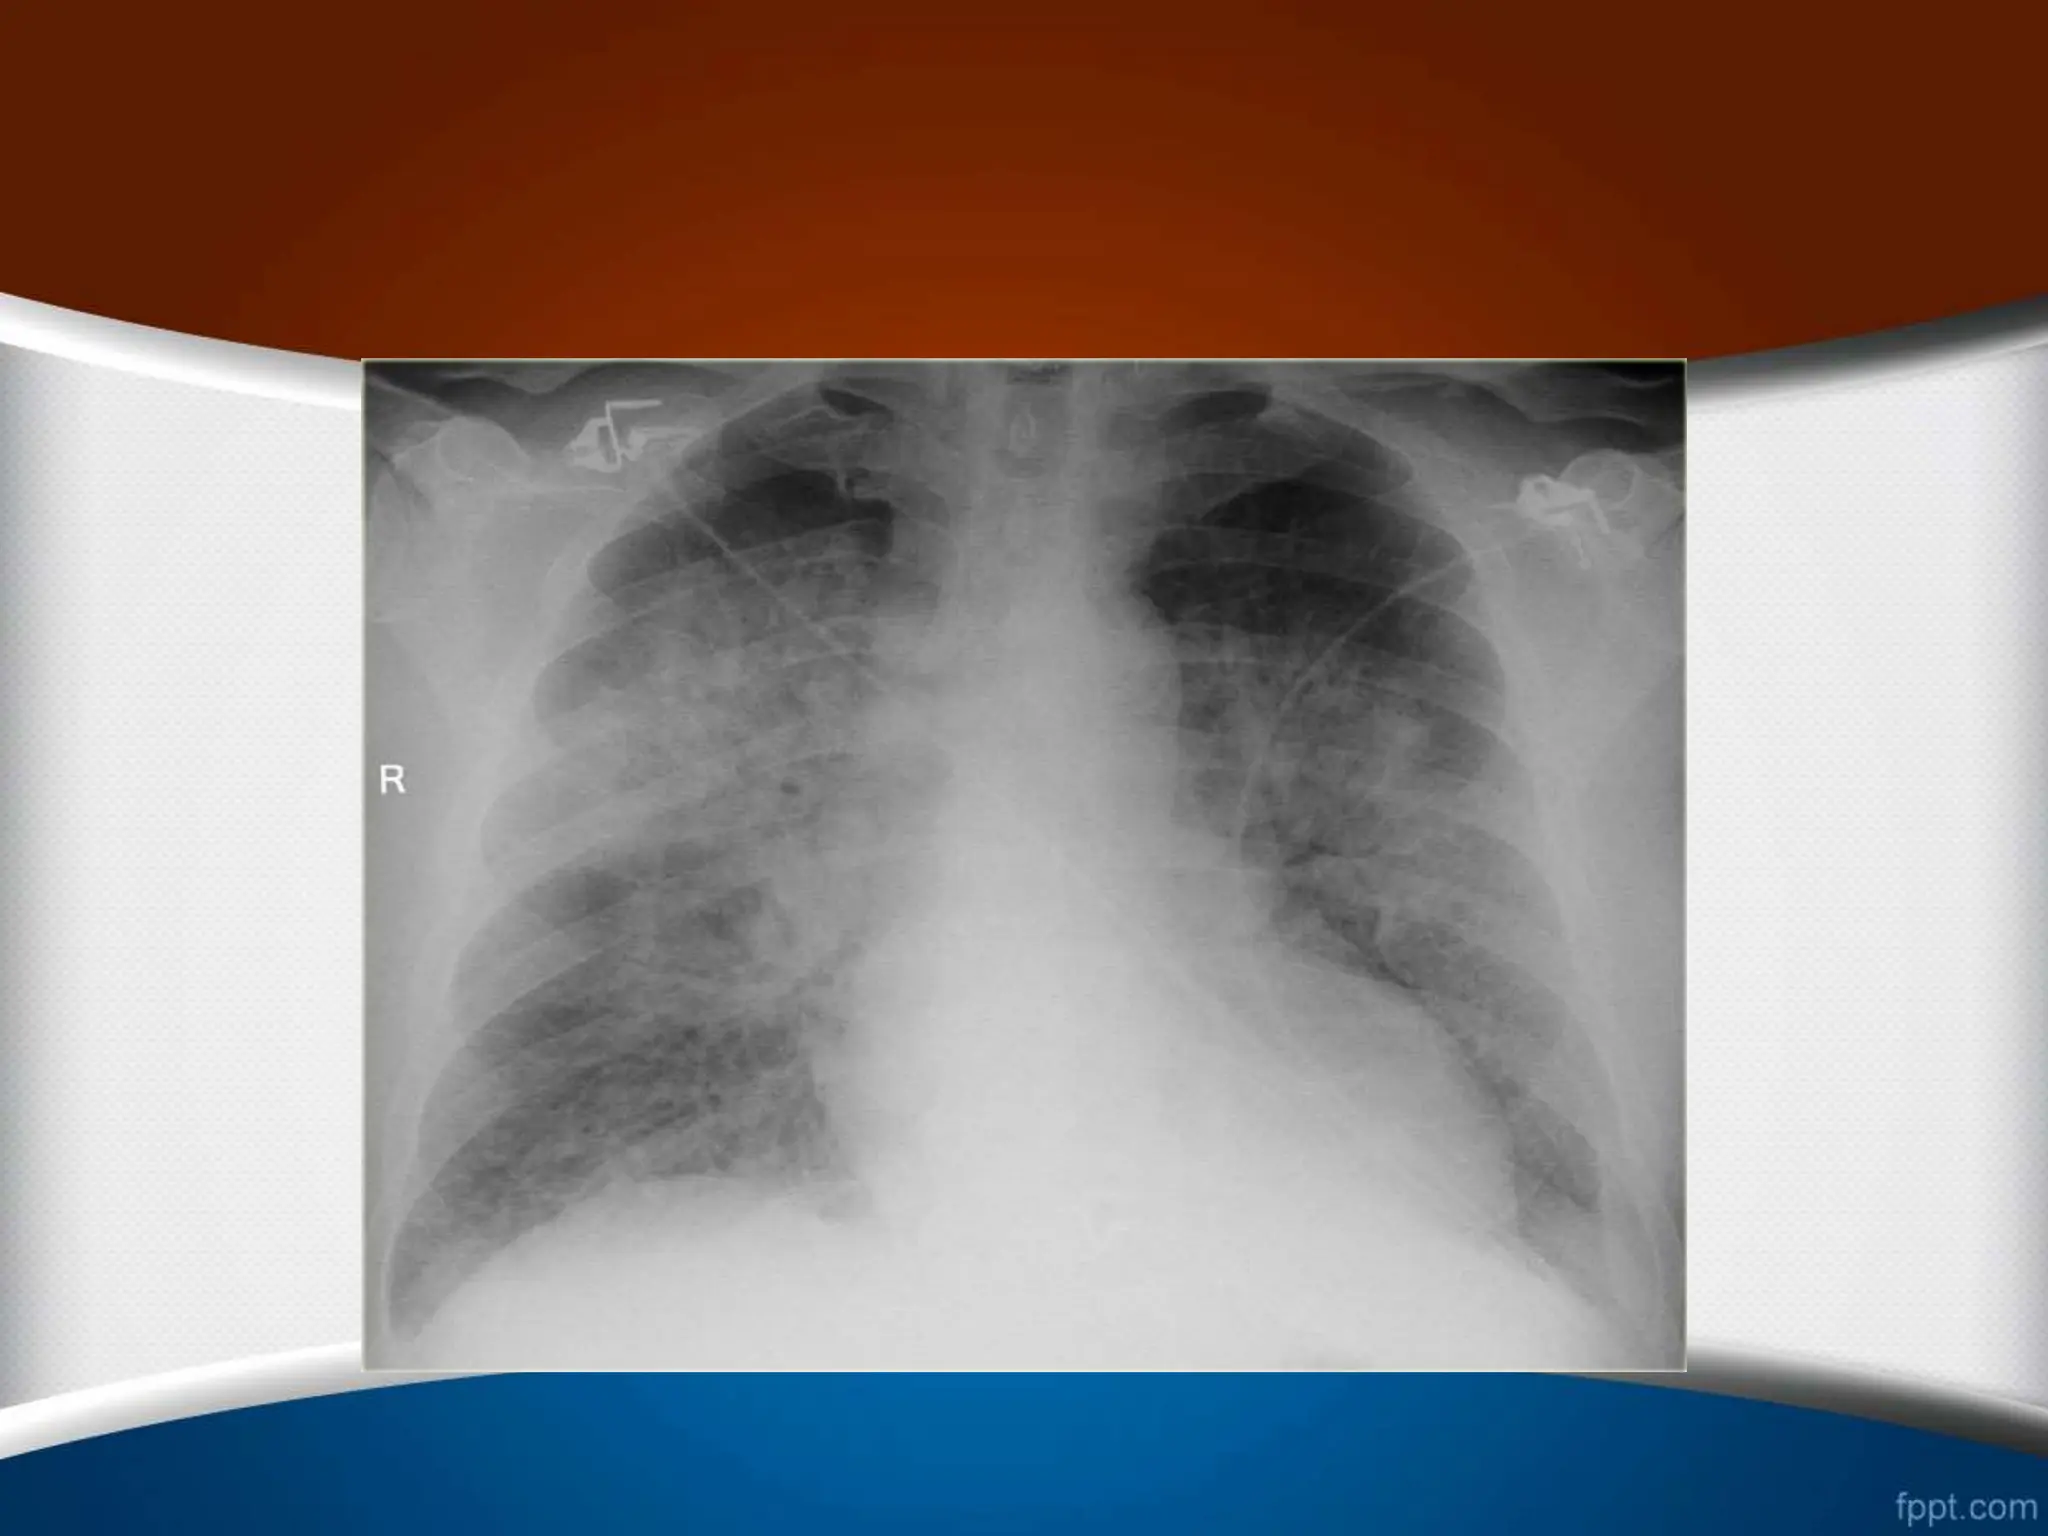

• #95 Pulmonary hypertension. Chest radiograph in a patient with secondary pulmonary hypertension reveals enlarged pulmonary arteries. This patient was found to have an atrial septal defect

• #96 Pulmonary Arterial Hypertension. Frontal radiograph of the chest shows an enlarged main pulmonary artery and a markedly enlarged right and left pulmonary arteries. The peripheral vasculature is normal.